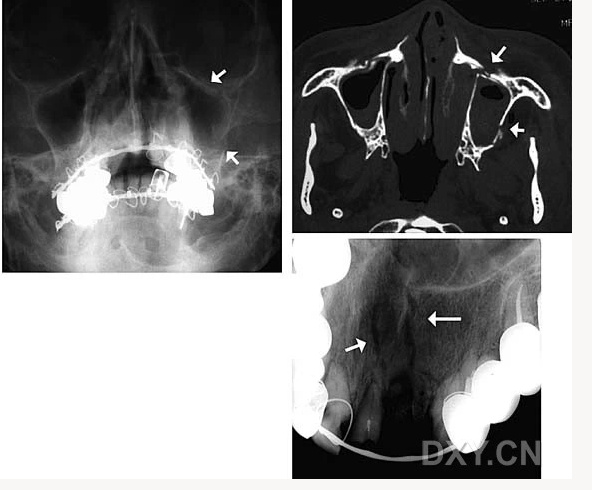

球狀上頜囊腫

含牙囊腫

球狀上頜囊腫    含牙囊腫

鼻腭囊腫

頜骨骨折